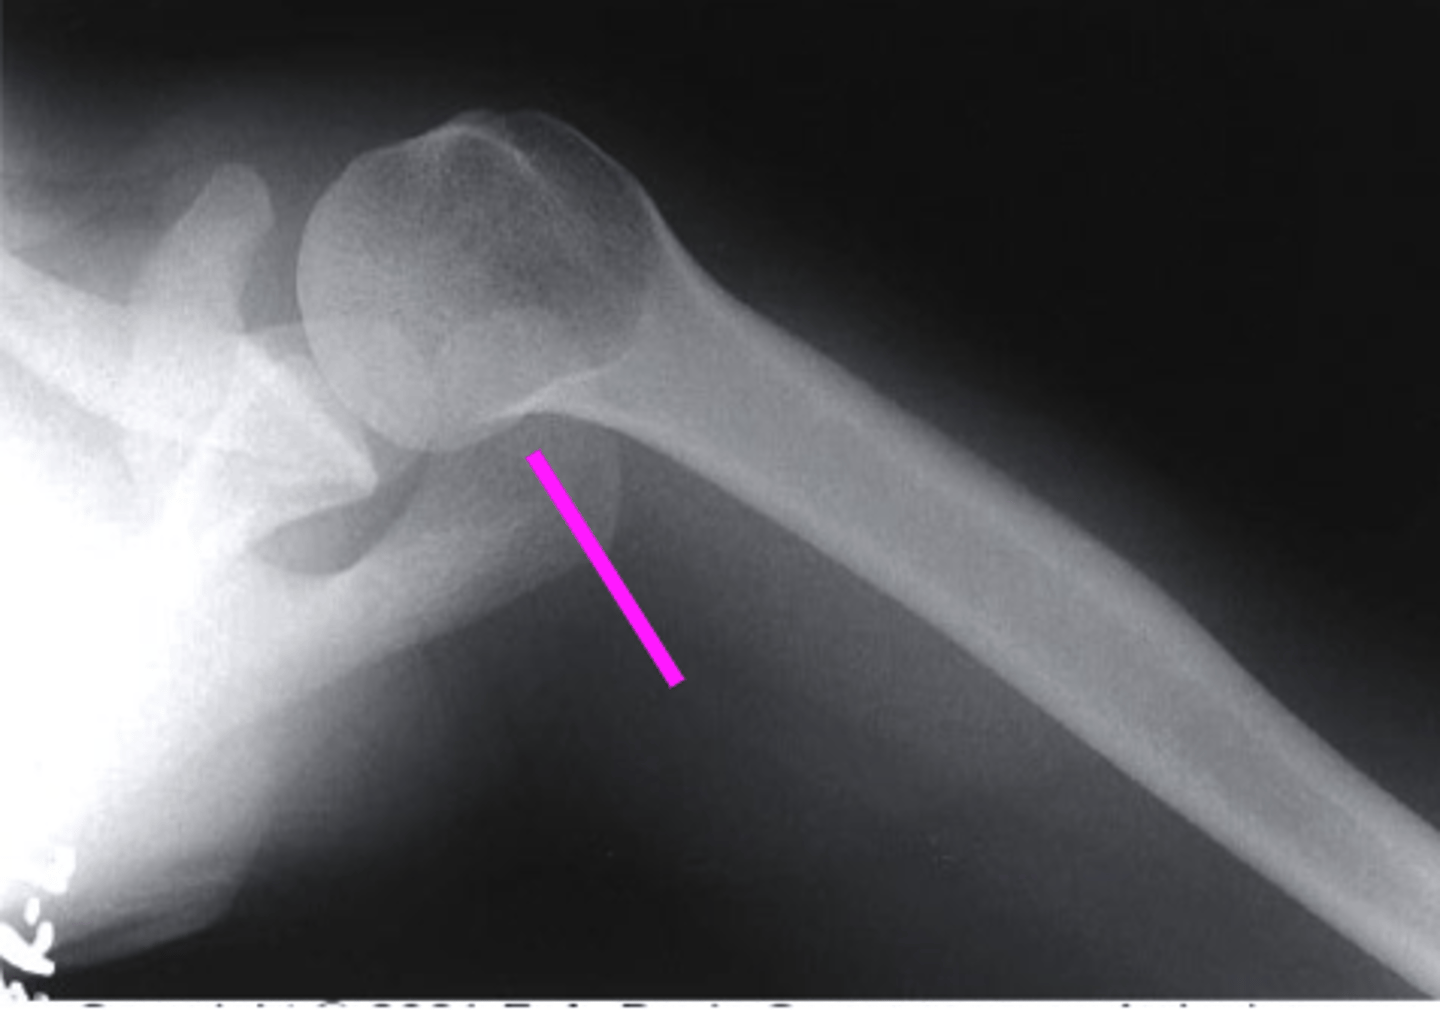

AP + IR

what view is this?

clavicle

what does the pink line point to?

spine of scapula

coracoid process

glenoid fossa of scapula

AC joint

acromion

Humeral Head

lesser tubercle